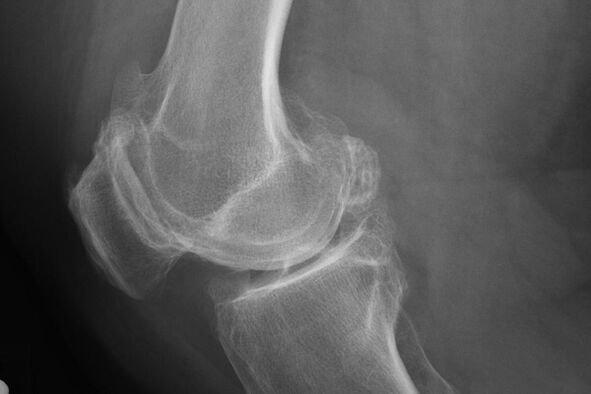

As a rule, the diagnosis of the disease at this stage occurs by accident, during an X -ray.On it, the doctor may note some irregularities on cartilage.It is also possible to narrow the lumen between the parts of the joint.

X -ray will help identify deviations in cartilage.

After the examination, the doctor prescribes the patient radiography.This is the main method of diagnosing arthrosis of the knee joint of any degree.

X -ray gives the doctor an idea of the changes occurring in the cartilage of the joint.However, in some cases, the initial stage may not be defined in the picture.

If necessary, the doctor may prescribe a repeated passage of an X-ray or computed and magnetic resonance tomography.